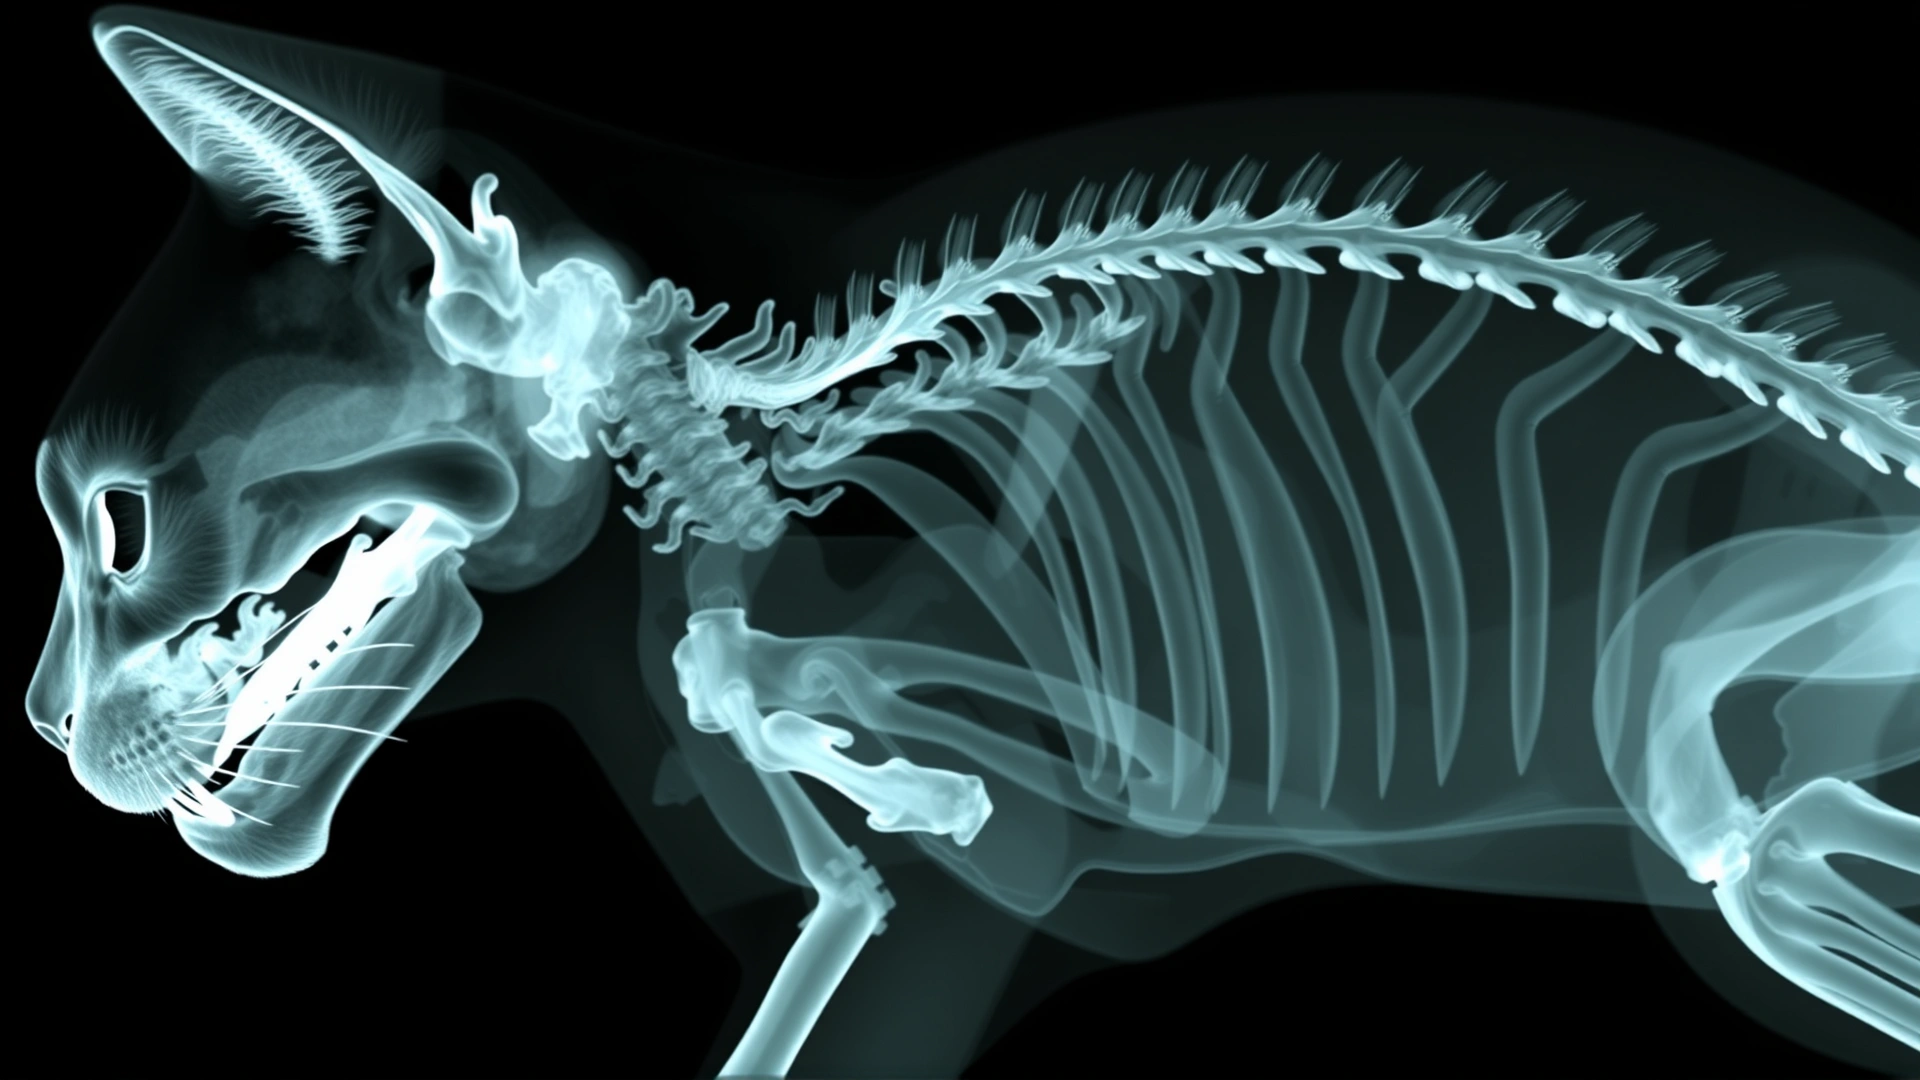

- التصوير الشعاعي (الأشعة السينية): للبحث عن أجسام غريبة أو توسع المريء.